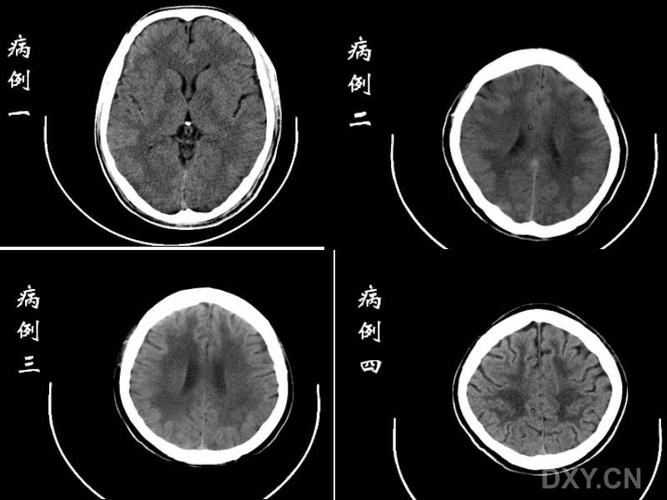

缺血性脑白质病变,脑白质缺血性改变

脑白质病变的影像学鉴别诊断

脑白质缺血性改变

脑白质病变

脑白质脱髓鞘病变

轻度脑白质变性

脑白质脱髓鞘改变

脑白质疏松